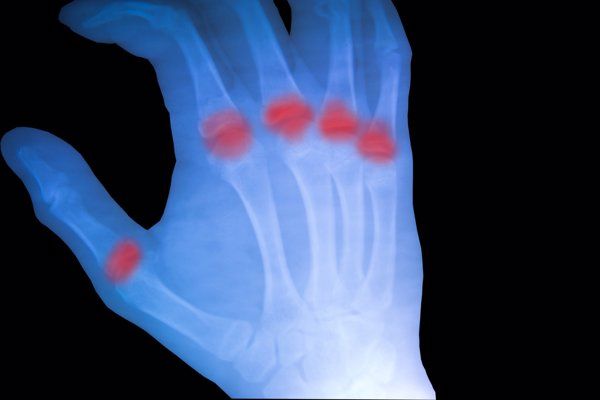

若患者存在类风湿性关节炎等疾病,在热水浴后也可能诱发或加重关节肿胀、疼痛等症状。因为热水浴会导致局部血液循环加快,炎症因子活跃度增加,从而加剧关节的炎症反应。